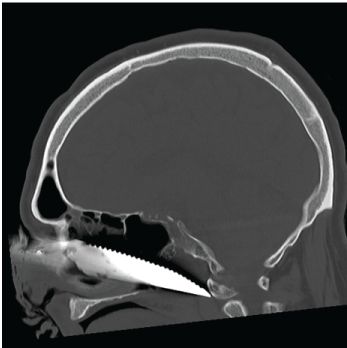

Because of the stable vital parameters we took the time to further investigate the knifeās trajectory. A plain X-ray showed the knife's position, outside the neurocranium, with the tip extending just anterior of the first cervical vertrebra (Figure 1 and Figure 2). To gain additional information regarding the structures in the face and the exact positioning of the knife a complementary enhanced CT scan with intravenous contrast was made (Figure 3). This scan showed the knife penetrating from the medial side of the orbita, along the maxillary sinus, through the medial pterygoid plate and nasopharynx, ending at the right anterior arch of C1. The eyeball and muscles are untouched, as well is the internal carotid artery.